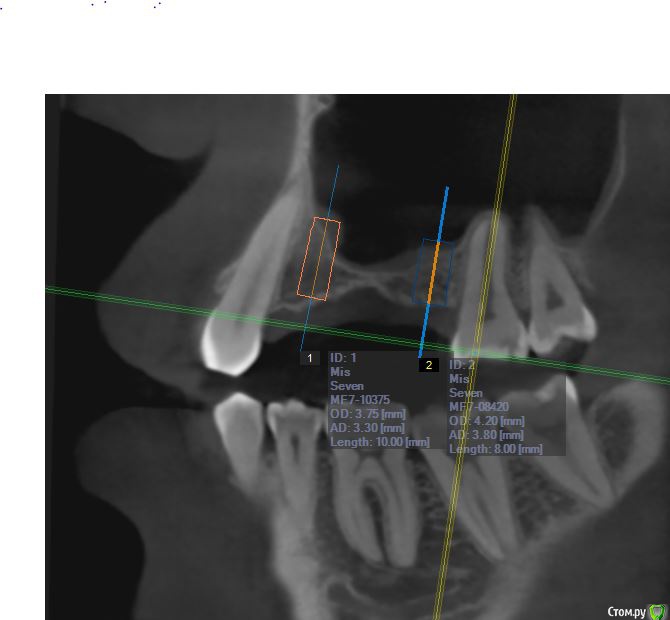

jm3300 Опубликовано 12 июля, 2016 Автор Поделиться Опубликовано 12 июля, 2016 А до операции КТ могли бы выложить? И сколько времени отсутствовали зубы в этой области?отсутствовали достаточно долги. КТ до: Ссылка на комментарий

jm3300 Опубликовано 14 июля, 2016 Автор Поделиться Опубликовано 14 июля, 2016 выкладываю кт Ссылка на комментарий

умножающий печаль Опубликовано 14 июля, 2016 Поделиться Опубликовано 14 июля, 2016 Промыть пазуху через соустье, курсом. Я отправляю к ЛОРам. Антибиотикотерапия, гипосенсибилизация. Один из винтов вестибулярно без костной поддержки, на мой взгляд. 1 Ссылка на комментарий

red_butler Опубликовано 15 июля, 2016 Поделиться Опубликовано 15 июля, 2016 гайморит всё таки есть?Не увидел, один винт похоже на выход 1 Ссылка на комментарий

red_butler Опубликовано 15 июля, 2016 Поделиться Опубликовано 15 июля, 2016 Пазуха чистая, Антон, какой винт на выход не понял?Может у пац аллергия ?На последних срезах, вестибулярно на 2/3 кости нет.Какая уж аллергия, если боль и отек 1 Ссылка на комментарий

умножающий печаль Опубликовано 15 июля, 2016 Поделиться Опубликовано 15 июля, 2016 Тоже не понял, вроде все хорошо стоят. Главное слизистые то в покое.Это пока в покое. Винт не покрытый костью, долго под мягкими тканями оставаться не будет. Неизбежна рецессия со всеми вытекающими. 1 Ссылка на комментарий